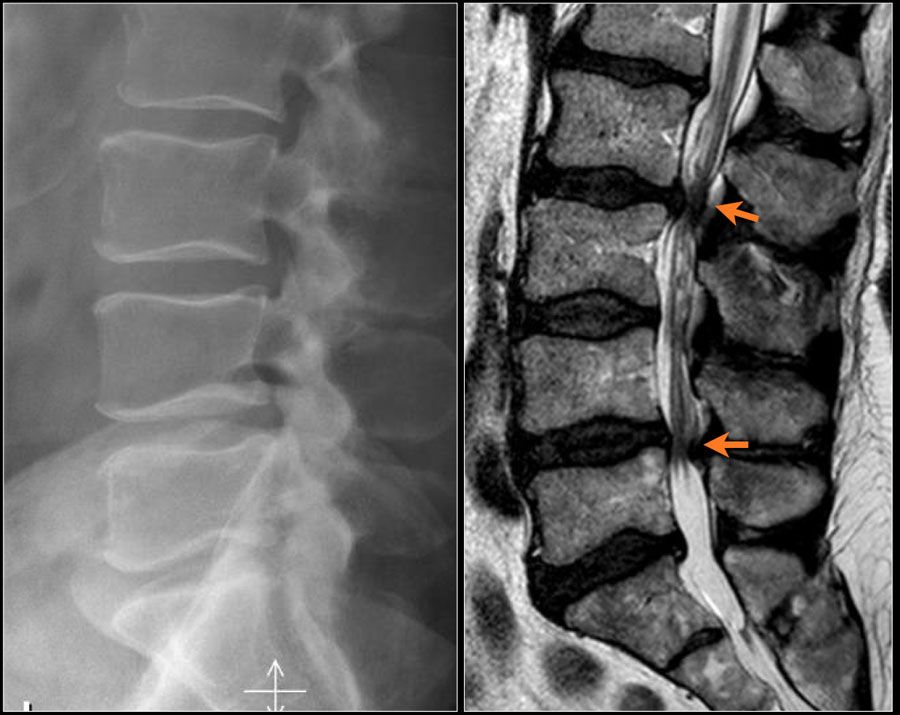

Сучасна діагностика стенозу: точні методи обстеження

Рентгенографія хребта

Дуже важливо при дегенеративних захворюваннях хребта проводити функціональну рентгенографію – при її виконанні пацієнт повинен максимально нахилитися вперед і назад. При необхідності робляться додаткові знімки з нахилами в сторони.

МРТ

МРТ є одним з найважливіших методів обстеження. При проведенні МРТ добре видно такі м’якотканинні структури, як:

- грижі,

- протрузії,

- нервові корінці,

- спинний мозок.

Як показано на малюнку, кожна зі структур може збільшуватися, викликаючи звуження вертебрального каналу або корінцевих каналів і стискати нервові структури (спинний мозок, корінці).